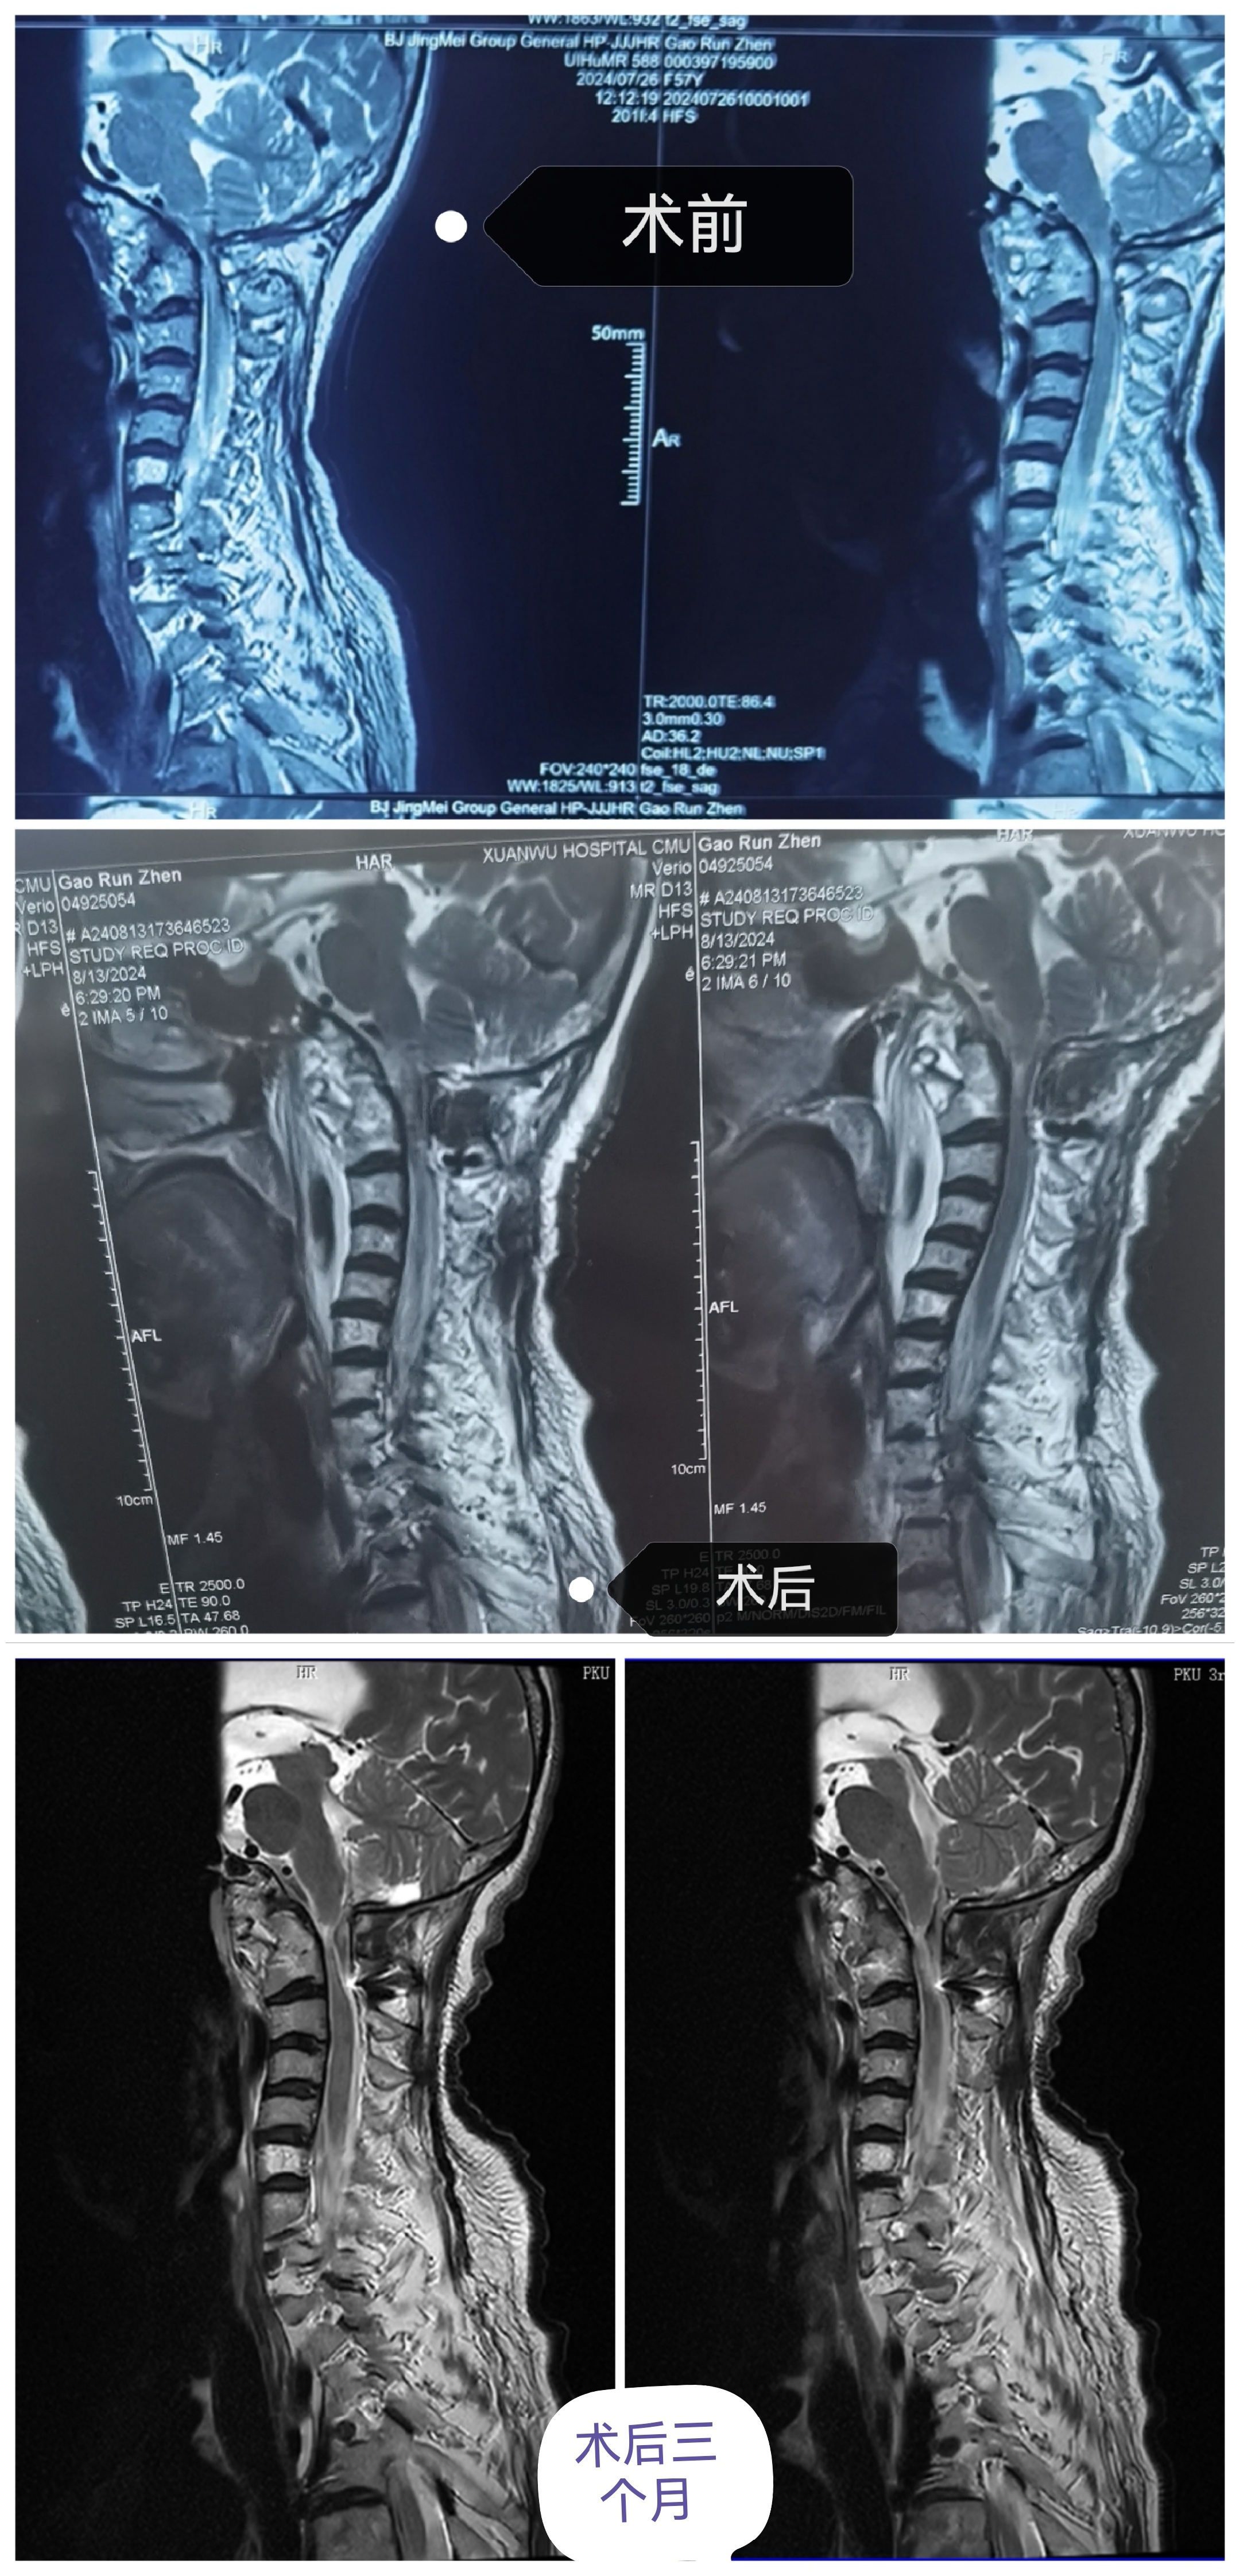

• 诊断:寰枢椎脱位

• 影像:

• 日期:2024.08.11

• 医院:宣武医院

• 主刀:陈赞

• 术后状况:术后症状加重,不能下床

• 术后影像: